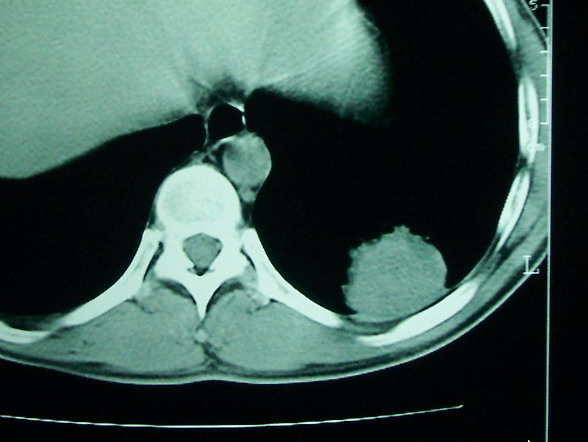

m      37y      发热   咳脓痰月余      ct肺脓肿但住院抗炎治疗后双肺内结节不知该如何解释

治疗后见左肺下野病灶较前缩小但双肺内结节影似无变化请较各位老师该如何下结论    治疗前wbc14.5 治疗后wbc 11.0

空洞内可见小结节样密度影考虑合并真菌感染

我看是不是可以两元化来解释,左肺下叶还是肺脓疡,而其余病灶考虑肺癌伴肺内转移,我看右肺上叶尖段病灶可见明显毛刺改变为原发病灶.

左下肺病灶除了明显的厚壁空洞 气液平外,明显见壁结节,另两肺多发小结节,综合考虑:左下肺周围性肺癌伴肺内转移.

鳞癌肺肺转移:厚壁空洞,洞壁厚薄不均,内似有壁结节,肺脓肿临床有无提示,血像如何?病灶周围很干净,没有明显渗出,很勉强?